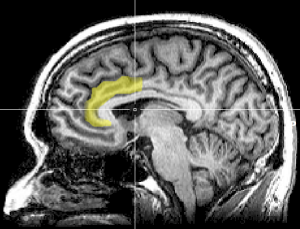

Corteccia Anteriore del Cingolo

La Corteccia Anteriore del Cingolo (CAC), indicato in giallo nella figura al lato, svolge diverse azioni tra cui la capacità di rilevare i conflitti, non solo emotivi, con la relativa percezione dell’errore nello svolgimento di un compito riguarda la gestione dello stress la CAC è coinvolta nella: